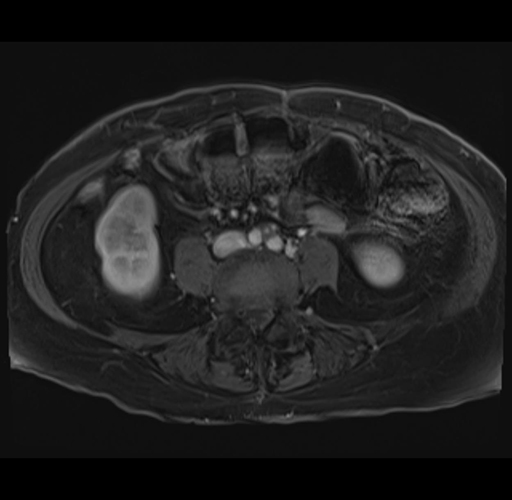

MRI T1

Imaging analysis

Based on your CT findings, which issue(s) would give reason for "planned slowing down moment(s)" in this case?

Considering a standard right hepatectomy procedure, what step(s) of the operation would you do differently in this case?